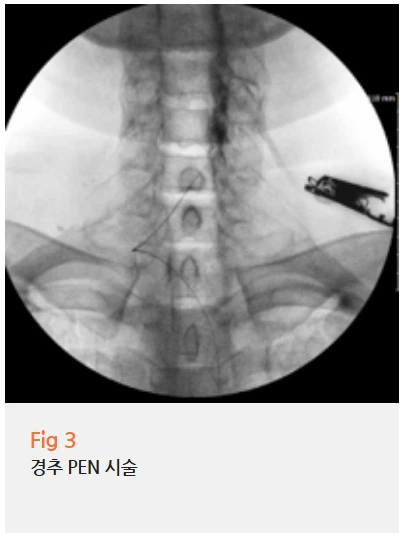

저는 환자분께 PEN 시술을 권해드렸습니다.

PEN은 'Percutaneous Epidural Neuroplasty'의 약자로,

가느다란 특수 카테터를 신경 주변까지 정밀하게 삽입해서

유착된 조직을 풀어주고 염증을 제거하는 시술이에요.

C-arm이라는 영상투시장치를 보면서 실시간으로 위치를 확인하기 때문에

눌린 신경 부위를 정확하게 타겟팅할 수 있습니다.

이 환자분처럼 협착증이 3군데나 있는 경우,

각각의 협착 부위를 정확히 찾아서 치료해야 하는데

PEN 시술이 가장 효과적이에요.